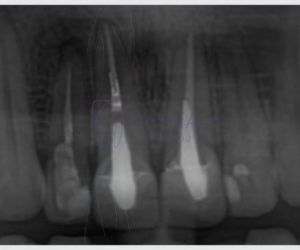

A indicação da extração de dente é uma notícia desagradável para a maioria das pessoas. Podemos afirmar que grande parte dos profissionais dentistas sempre trabalha para preservar ao máximo um dente, e, portanto, a indicação da extração dentária normalmente só ocorre quando o dentista identifica qu…